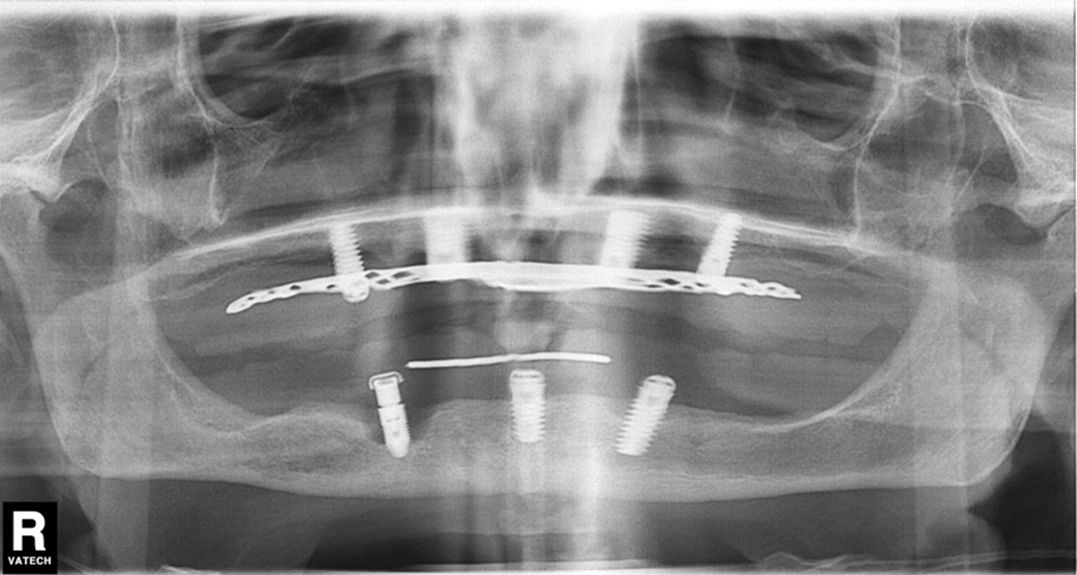

A continuación, os mostramos el cambio de un paciente tras su tratamiento periodontal:

En este caso, el paciente presentaba periimplantitis en la zona de 43, la cual evolucionó satisfactoriamente tras el tratamiento periodontal.